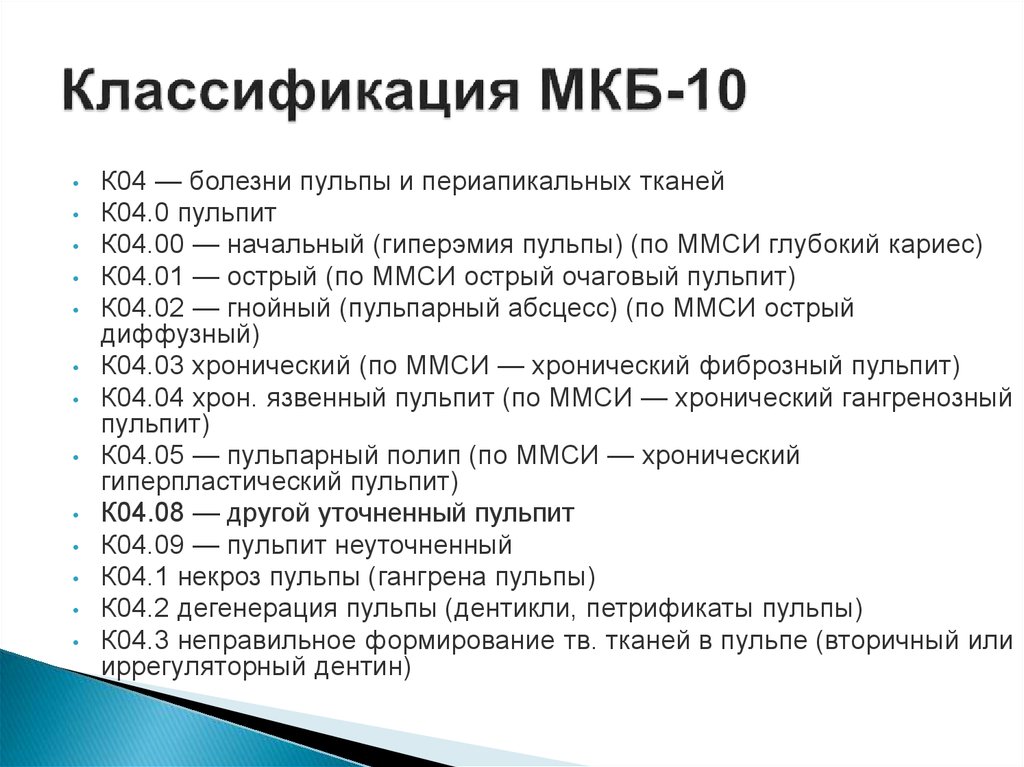

Код мкб 10 атерома головы

Код мкб 10 атерома головы 109 фото